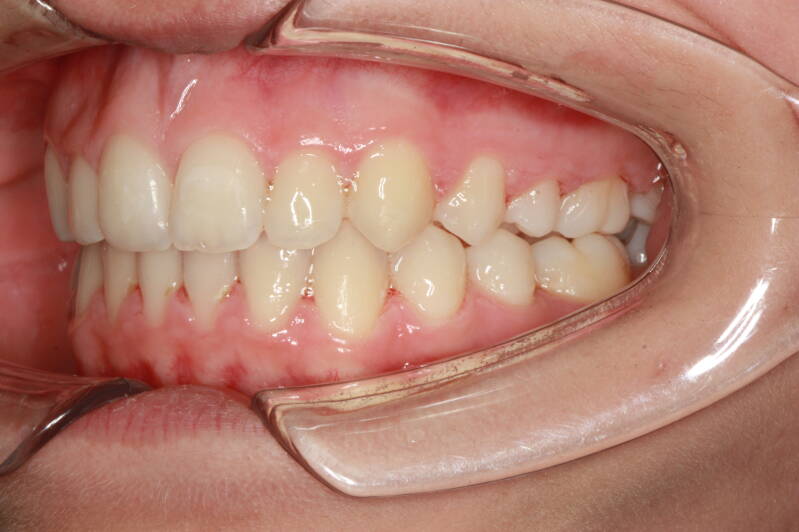

Questo mese vi presentiamo G.G. f. di15aa. Ha una seconda classe suddivisione destra molare e canina. richiesta Allineamento.

FOTO INIZIALI PRE TRATTAMENTO ORTODONTICO